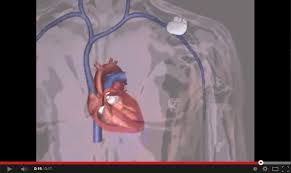

You take medications that slow down your heartbeat. It is made up of flexible wires (leads) with sensors, a battery, pulse generator, and a small computer. It produces the electrical impulses that cause your heart to beat. Bradyarrhythmia is the main indication for implantation of a pacemaker. It helps control your heartbeat. In most cases, people can completely forget they have a pacemaker at all other times. Depending on your condition, you may have a pacemaker with one to three flexible, insulated wires (leads) placed in a chamber, or chambers, of your heart. During the procedure, patients only need local anesthesia.

However, if your doctor has done tests and diagnosed you with bradycardia, you may need a pacemaker to maintain a healthy heart rhythm. It produces the electrical impulses that cause your heart to beat. The pacemaker might not be able to detect or correctly treat your heart rhythms. At the airport, let the tsa agent know that you have a pacemaker. It's a small mass of specialized cells in the top of the right atrium (upper chamber of the heart). During the procedure, patients only need local anesthesia. Pacemakers are implanted to protect the device and give electrodes access to the heart. A chamber of the heart contracts when an electrical impulse or signal moves across it.

Pacemakers are implanted to protect the device and give electrodes access to the heart. However, if your doctor has done tests and diagnosed you with bradycardia, you may need a pacemaker to maintain a healthy heart rhythm. Here are some of the most common causes of arrhythmias: Your heart's natural pacemaker — the sinus node — produces electrical impulses to stimulate your heart to beat. What a pacemaker does is keep the heart beating at the proper rate and from beating too slow. Bradyarrhythmia is the main indication for implantation of a pacemaker. This type of pacemaker is only available for a small percentage of people who need pacemakers, but for those who qualify, it significantly reduces surgical risks and recovery time. The pacemaker may deliver pacing therapy when it is not needed. Why is a pacemaker implanted? Your doctor may ask you to stop taking certain other medications. You may need to undergo a separate security procedure, such as screening with a hand. The pacemaker may not work properly and not deliver therapy as expected. Remember your pacemaker when you arrive at the airport or other public places with security screening.